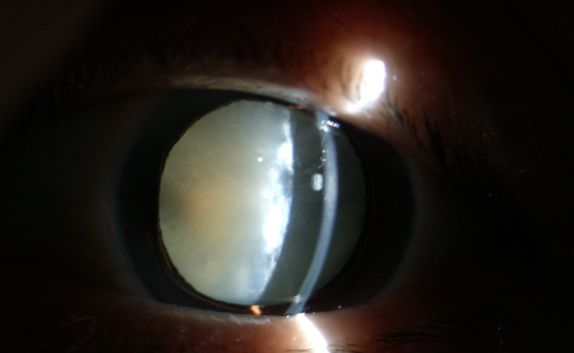

白內(nèi)障癥狀

糖尿病患者合并白內(nèi)障盡早手術(shù)的原因:白內(nèi)障發(fā)生后,不但使患者視力產(chǎn)生障礙甚至失明,還直接影響到醫(yī)生對眼底的檢查和治療,因為渾濁的晶狀體阻斷了進(jìn)出光線。因此,糖友們的白內(nèi)障手術(shù)治療,既能解除視力障礙,還能掃除糖尿病視網(wǎng)膜病變的檢查、治療障礙,所以應(yīng)盡早手術(shù)。